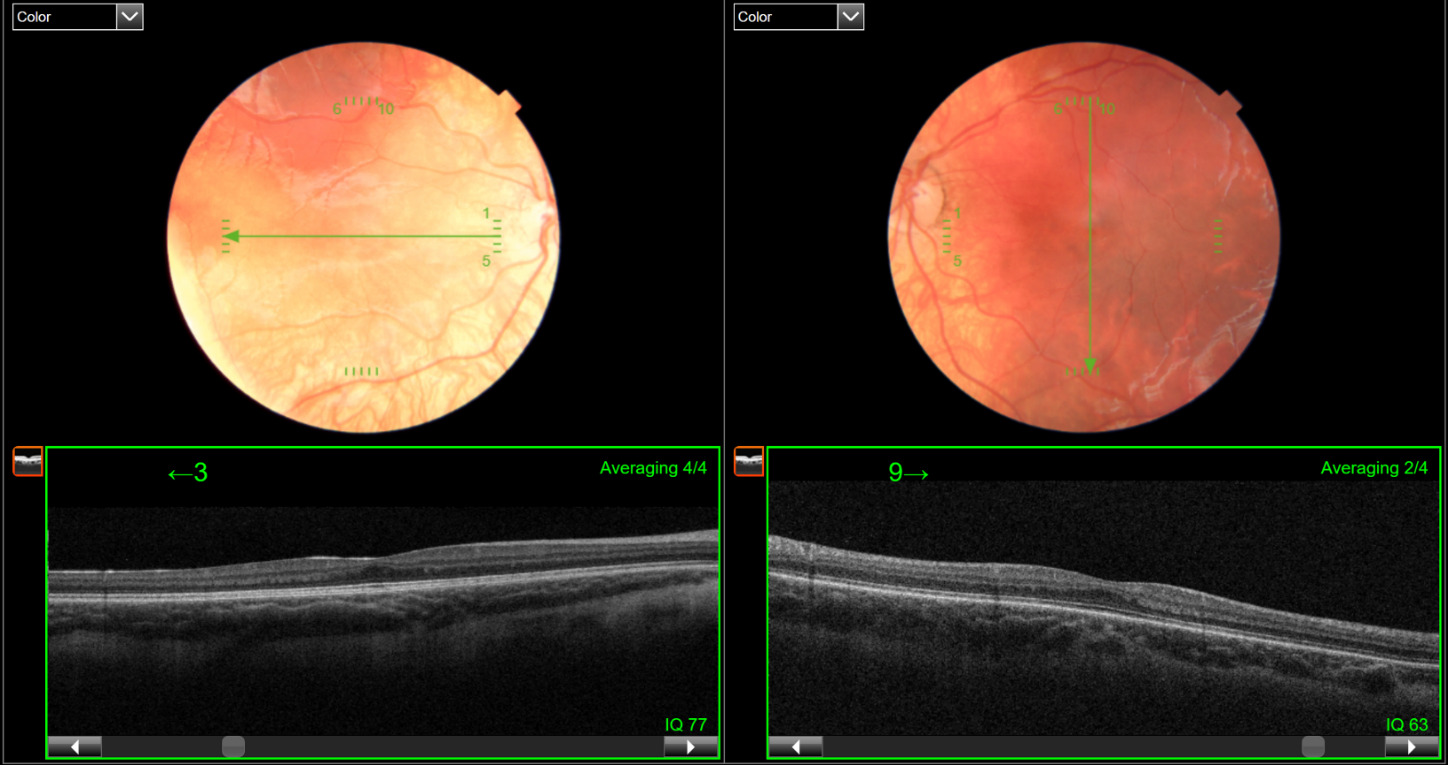

A 9-year-old boy was referred by an eyecare provider for the evaluation and treatment of anisometropic amblyopia. He had been wearing glasses for at least 3 years, and a previous magnetic resonance imaging and other medical history were unremarkable. The patient’s best-corrected visual acuity through +3.00 -0.75 x 165 in the right eye and +4.00 -0.75 x 170 in the left eye was 20/40 and 20/60-, respectively, measured with single letters and crowding bars. The preceding prescription was based on a +0.25 diopter spherical reduction in each eye from a cycloplegic refraction conducted by the referring provider. The extraocular muscles showed full range of motion, but there were saccadic intrusions with small amplitude horizontal nystagmus, which dampened in right gaze and with convergence. There was not a notable latent component to the nystagmus. Amplitude of accommodation was significantly lower than expected for his age; however, accommodative response accuracy was normal. Cover testing through his spectacle prescription measured 6 prism diopters esophoria at distance and 14 prism diopters of left esotropia (90%) at near. The near esodeviation decreased to 10 prism diopters through a +2.00 diopter add, indicating a gradient accommodative convergence-to-accommodation ratio calculation of 2 prism diopters of convergence per diopter of accommodation. Further specific accommodative and binocular findings are listed in Table 2. A foveal reflex was not observed during the dilated ocular health evaluation. A 5-line raster optical coherence tomography was performed, which confirmed grade 1 foveal hypoplasia (see Figure 2).

A collage of images of a human eye AI-generated content may be incorrect.

Figure 2.5-line raster optical coherence tomography scans of both the right and left eye, showing grade 1 foveal hypoplasia of each eye.

A 7-year-old boy presented for his annual examination to monitor his refractive amblyopia, secondary to hyperopic anisometropia and bilateral high astigmatism. Medical history was positive for Waardenburg syndrome type II, specifically a deletion of exons 5 through 9 of the MITF gene, a gene which can be associated with albinism.10,11 Waardenburg syndrome is associated with deafness and iris heterochromia, both of which were present in this patient. The patient had bilateral cochlear implants to address the hearing loss. Waardenburg syndrome is also frequently associated with a white forelock and large pupillary distance, which were not present in this patient but were present in his mother who also has been diagnosed with the condition. His parents expressed a desire to optimize his vision, especially given the language and speech delays secondary to his deafness. Measures of visual acuity from previous examinations had been inconsistent because of age, speech delays, and cooperation during the examinations. He had been in glasses with full hyperopic correction since age 3 years and had previously attempted patching, with a few sessions of vision therapy to improve visual acuity and stereopsis. At the current examination, best-corrected visual acuity measured using HOTV single letter with crowding bars was 20/40 in each eye. His habitual prescription was +3.75 -2.50 x 180 in the right eye and +5.25 – 2.50 x 001 in the left eye, with a +2.50 add for a previously diagnosed high esophoria at near. This prescription was based on cycloplegic retinoscopy, with the full hyperopic power incorporated to reduce the patient’s esophoric alignment. At this visit, cover test findings measured orthophoria at distance and 6 prism diopters of esophoria at near through the bifocal, without measurable random dot stereopsis. The patient was able to pinch the Stereofly wings above the page and exhibited fusion at all distances in dark and bright illumination with the Worth Dot test. The dilated fundus examination revealed bilateral hypopigmented fundi, which was more evident in the right eye. Given the poor improvement in acuities with prior amblyopia treatment and the fundus appearance, a 5-line raster optical coherence tomography was performed, which revealed grade 1 foveal hypoplasia in both eyes (see Figure 3). A pattern reversal visual evoked potential was also conducted to derive an objective estimate of the potential visual acuity of the patient, which enabled an assessment of the veracity of the subjective acuity measures. Potential visual acuity estimates were based on a regression model developed at the Michigan College of Optometry using the LKC 5-step pattern reversal visual evoked potential protocol.12 Results from the pattern visual evoked potential estimated a best-corrected visual potential of at least 20/30 binocularly. A full-field flash electroretinogram was also conducted, which ruled out cone- and rod-mediated retinal dysfunction. No further visual treatment was recommended at this time based on the cumulative results of clinical testing.

Figure 3.5-line raster optical coherence tomography scans of the right and left eye, demonstrating grade 1 foveal hypoplasia in each eye, and reduced choroidal pigment in the right eye.